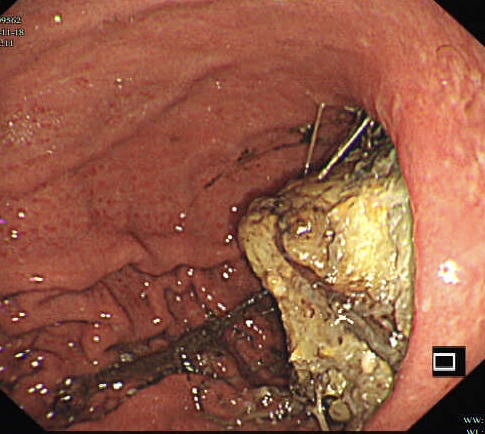

第二个病例,青年男性,也是突然腹痛,症状和第一个类似,首选腹部CT。

胃镜证实

同样治疗后痊愈出院